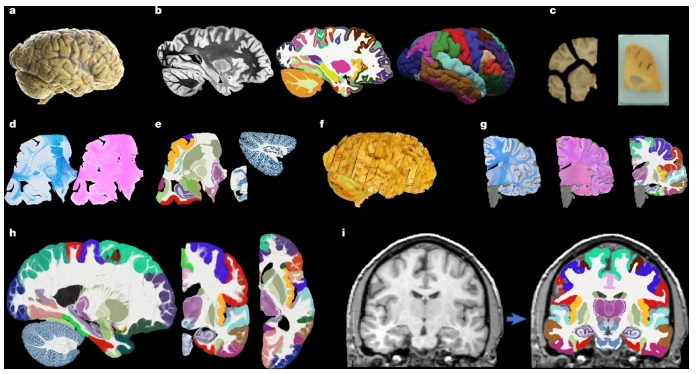

近日,一篇发表在国际杂志Nature上题为“A probabilistic histological atlas of the human brain for MRI segmentation”的研究报告中,来自伦敦大学学院等机构的科学家们通过利用AI技术成功构建出了全球首个全脑概率性组织学图谱—NextBrain,这项历时六年的工程不仅将大脑图像的精度推向了前所未有的高度,更让科学家能在几分钟内就能从活人的MRI扫描中识别出333个大脑区域,甚至包括海马体中那些微小的“子街区”。

构建NextBrain的过程堪称一场科学与耐心的极限挑战,文章中,研究人员从五个完整的人脑半球中切出了近一万张组织切片,每一片都被染色、显微拍摄,再通过AI技术重新拼接成三维数字模型,就像用十万块没有参考图的拼图复原出一座精密的城市。没有AI,研究人员可能得花上几十年时间,AI不仅负责对齐图像、填补缝隙,还学会了在MRI与组织学图像之间“翻译”,让活体扫描也能映射到细胞级别的结构。

最终,研究人员在五个大脑的3D模型上标记了333个区域,并将其融合成一个“标准成人脑”—一个适用于所有人的通用脑图谱。